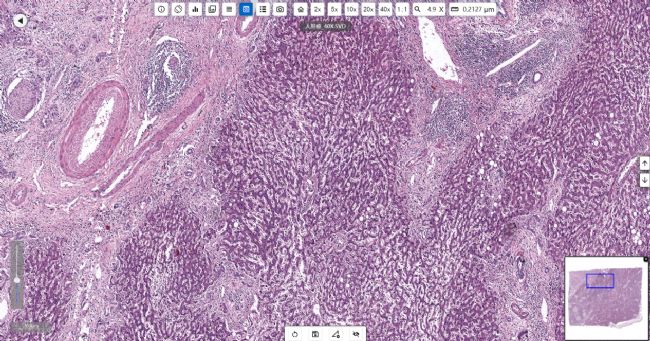

肝癌:肝臟的惡性腫瘤,其細(xì)胞來(lái)自肝臟的上皮組織,包括肝細(xì)胞和膽管細(xì)胞等。

明美切片掃描儀MDS4掃描的人肝癌切片